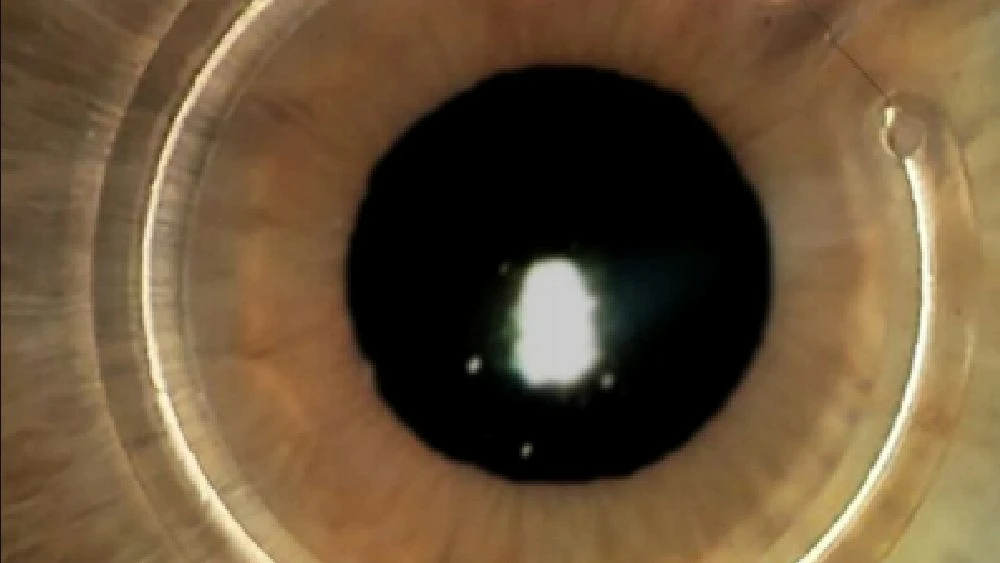

O ceratocone é uma doença da córnea que provoca afinamento e deformação progressivadessa estrutura, deixando-a mais curva e irregular. Essa alteração causa visão embaçada, distorcida e aumento frequente do grau,principalmente astigmatismo.

O ceratocone é uma doença da córnea em que ela fica mais fina e assume um formato irregular, parecido com um cone. Isso causa visão borrada, distorcida e dificuldade para enxergar.

O crosslinking é um procedimento que fortalece a córnea, impedindo a progressão do ceratocone. É atualmente o principal tratamento para estabilizar a doença.